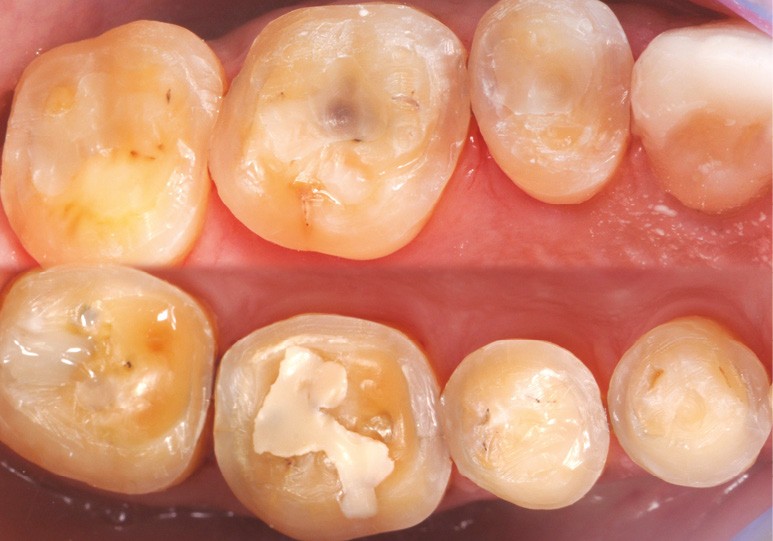

Les overlays (céramique et composite) sont devenus en quelques années un véritable référentiel en termes de restaurations partielles postérieures. Ils sont même les successeurs contemporains de la couronne périphérique dans bon nombre de situations, que ce soit sur dent pulpée présentant un délabrement coronaire important ou sur dent dépulpée pour laquelle le recours au recouvrement de la totalité de la face occlusale est souvent jugé plus indiqué (fig. 1 à 4).

Leurs indications cliniques sont particulièrement fréquentes dans les contextes d’usure érosive pour lesquels il est souvent nécessaire d’augmenter la dimension verticale d’occlusion (DVO) afin d’ouvrir l’espace anatomique antérieur (fig. 5 et 6). Leur dénomination, qui dépend de leur niveau de recouvrement, varie du table top (fig. 7) au veneerlay (recouvrement des faces occlusale et vestibulaire sur de faibles épaisseurs et en intra-amélaire) (fig. 8 et 9). Mais leur indication est aussi posée sur les dents fissurées (« craked tooth syndrome »), dans les cas de dents présentant une fragilisation cuspidienne ou encore en présence d’une dent postérieure en infraposition occlusale.

à ces restaurations correspond aujourd’hui toute une série de nouveaux design postérieurs permettant une ultra-préservation tissulaire et pouvant s’inscrire, en fonction des situations cliniques, dans l’émail (situation idéale), dans la dentine, dans le composite de base intermédiaire, ou un « mix » de ces différents supports (fig. 10 à 13).